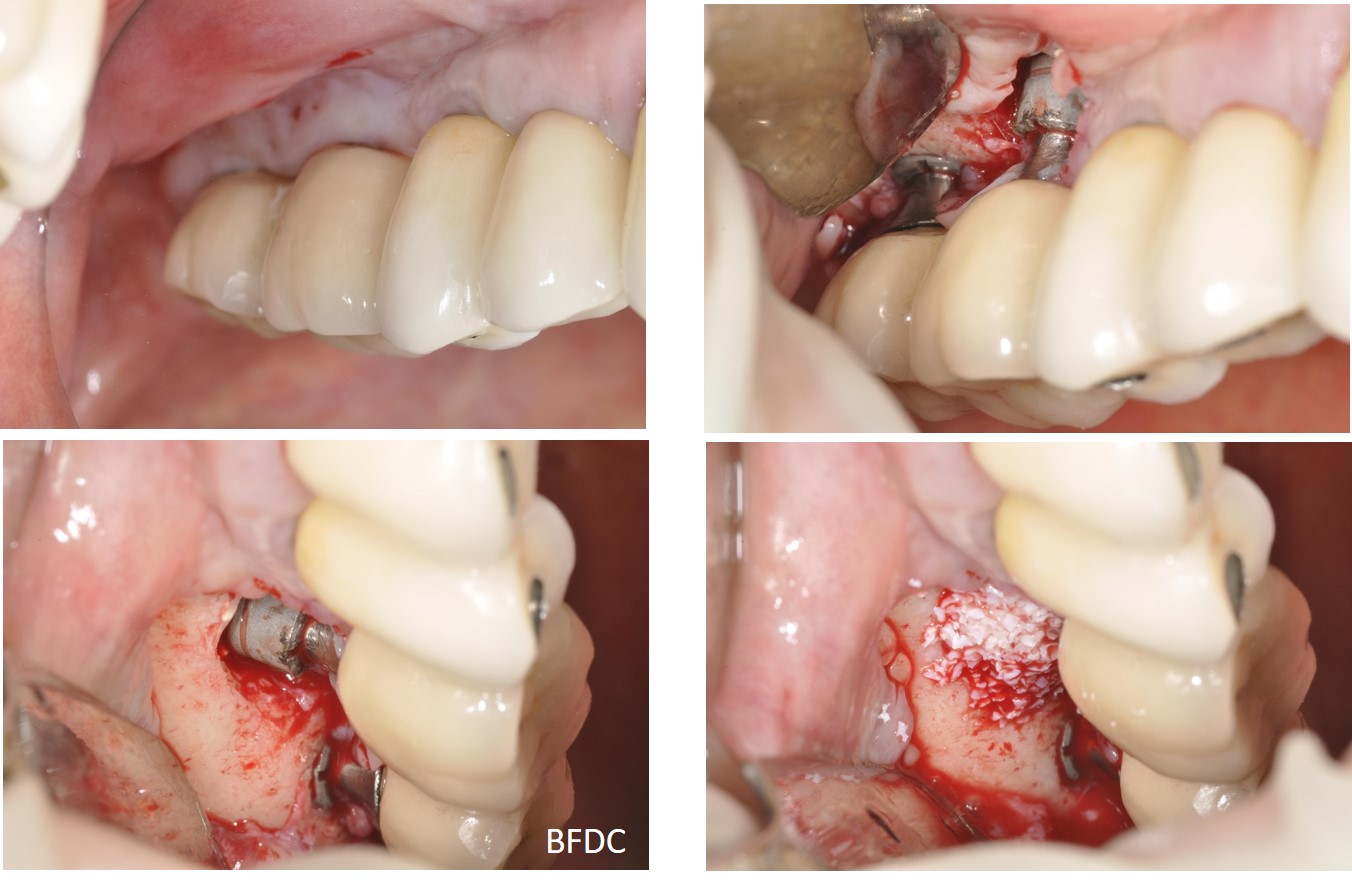

植體清創、並施予骨粉

植體周圍疾病,因影響破壞的程度不同,治療的方式亦有所不同。一般可分為非手術性治療及手術性治療。 一、非手術性治療一般有下列幾種方式:1.機械式清創;2.殺菌治療;3.抗生素治療;4.雷射治療。對於侷限在軟組織之植體周圍黏膜炎,非手術性治療幾乎都可解 決。而破壞到周遭骨頭的植體周圍炎,仍會先以非手術性方法來治療。當非手術性治療無法達到目標時,則會進行手術性治療。 二、手術性治療,包括了清創,植體表面去感染,必要時利用骨移植物及再生膜,進行引導骨再生手術(Guided Bone regeneration)重建植體周圍硬組織。